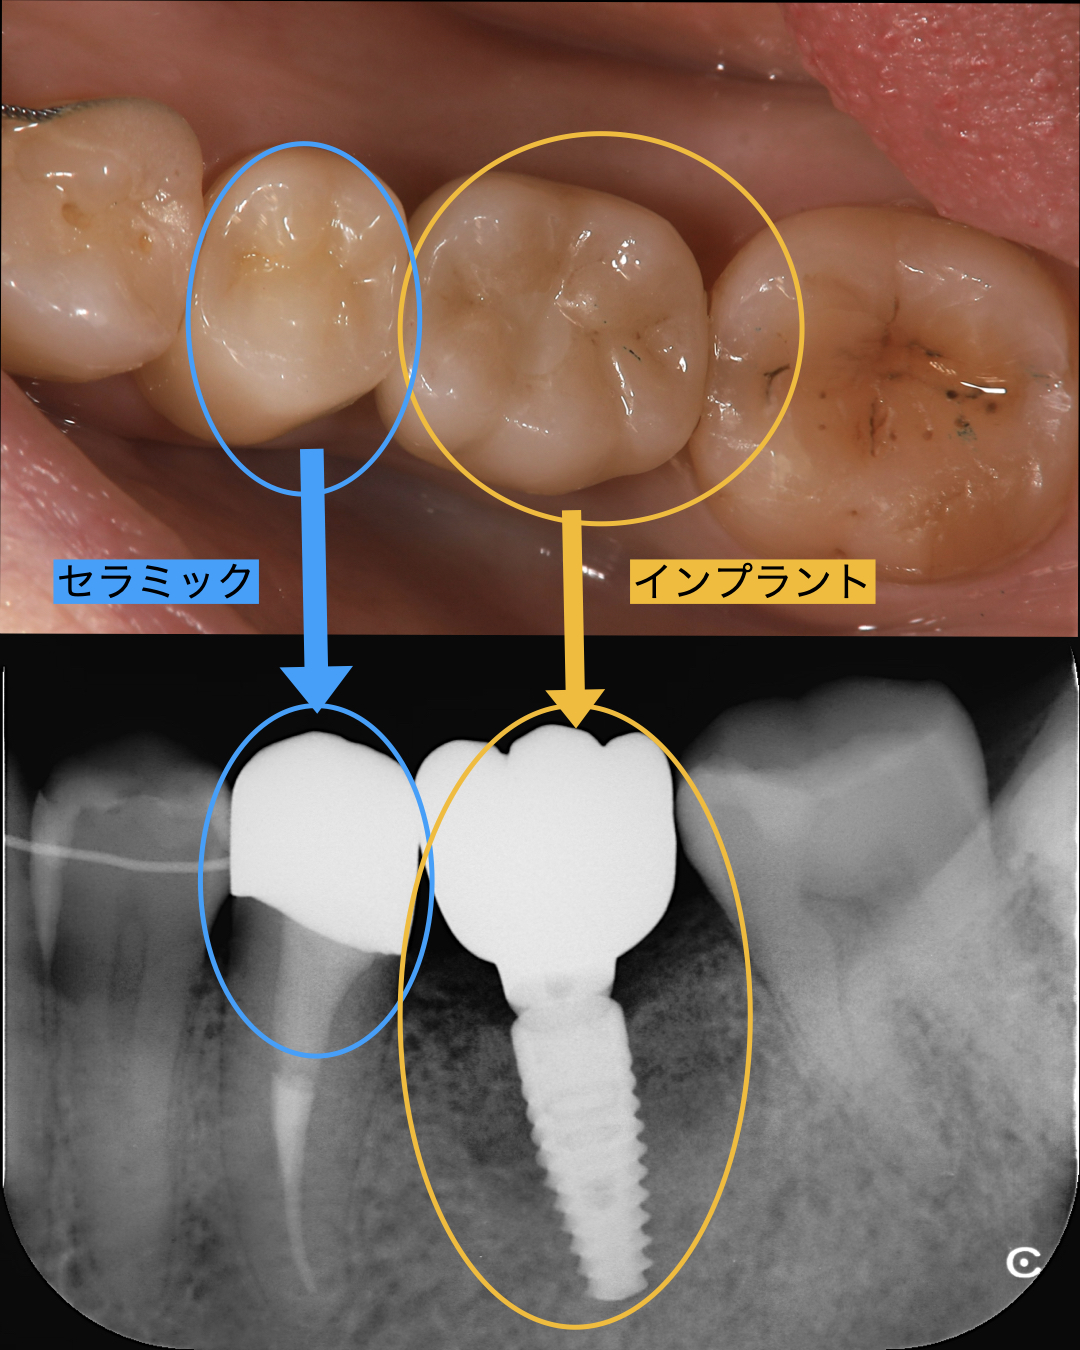

患者様は左下の奥歯で奥で噛むと痛いというお悩みで来られました。お口の中もみると食いしばっている跡がみられ、今までも他の歯も食いしばりによる破折が何度かあったそうです。左下の奥歯を診させて頂くと以前に、根の治療を行っており、歯質もすくなく、破折の可能性が高い状態でした。精査しCT撮影などを行うと歯牙が破折、すなわち割れており保存不可能と診断しました。 患者様に説明をし、インプラント治療を希望されたので抜いてその日にインプラントを入れる、抜歯即時インプラントを行うことにしました。

インプラントを行う手前の歯牙も根の先にウミがあり治療を先に行いました。

手術当日は、まずは歯を抜いてキレイに掻爬を行いました。さらに続けてインプラントを入れる穴をあけインプラントを埋入しました。歯を抜いて、その日にインプラントを埋入する抜歯即時インプラントという手法で行いました。

術後の患者様の感想

| 治療内容 | 奥歯1本のインプラント、セラミック治療1本 |